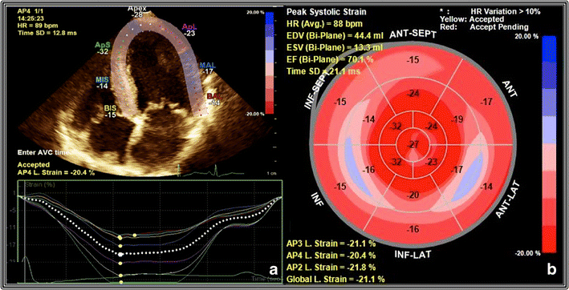

Strain Echocardiography (Speckle-Tracking Echo)

Strain Echocardiography (Speckle-Tracking Echo) – Advanced Heart Function Analysis in Delhi Strain Echocardiography—also known as Speckle-Tracking Echocardiography—is an advanced cardiac imaging technique used to assess subtle abnormalities in heart muscle function, even before conventional 2D Echo shows changes. At Heart n Health Cardiology Clinic, we are among the very few centers in Delhi offering this high-end test under the expert care of Dr. Shadab Samad (MBBS, MD, DNB – Interventional Cardiology).

Strain Echocardiography (Speckle-Tracking Echo) is especially valuable for:

Strain Echo uses advanced software on the Philips Affiniti 70 to track motion of individual myocardial segments. It calculates “Global Longitudinal Strain (GLS),” a sensitive marker of heart muscle health—often altered before changes in ejection fraction (EF) appear.